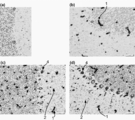

- the figure substitute photograph which shows the result of the immunohistochemical staining for the anti- hTfR antibody of the cerebral cortex of the cynomolgus monkey after the single intravenous administration of the anti-hTfR antibody.

- A Non-administration of anti-hTfR antibody, (b) administration of anti-hTfR antibody No. 1, (c) administration of anti-hTfR antibody No. 2, and (d) administration of anti-hTfR antibody No. 3.

- the bar on the lower right of each photograph is a gauge representing 50 ⁇ m.